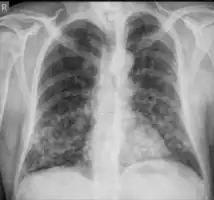

Chest X-ray: Nodular shadows both lungs

CT chest: Paracoccidioidomycosis